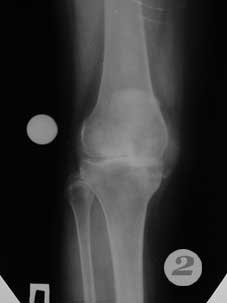

Рис. 1,2 - состояние до операции

примеры операций